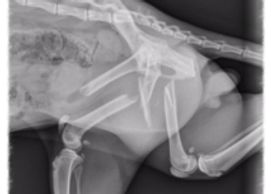

In late March of 2016, PAL received a distraught phone call from the caretaker of a stray cat that had been hit by a car. His back legs were immobile and his caretaker could not afford to take him to the vet for further care or humane euthanasia. After hearing the seriousness of the situation, it was decided that the most humane thing to do would be to euthanize him to put an end to his suffering. When she got to PAL with the cat, Sabbat (at that time named “Wadya”), Dr Asbury did an exam and soon found out that the situation was not nearly as bad as it seemed and at his caretaker’s delight, we agreed to keep him at PAL and develop a plan to get him better! Dr. Asbury took Sabbat to a local full service vet where they did x-rays and confirmed some bad news. Sabbat had two fractured femurs which required serious and complicated surgery. Sabbat’s amazing personality and will to live quickly enamored all the staff at PAL and after a full day of surgeries, Dr. Asbury did the three hour procedure to repair his fractured femurs. After a successful recovery and lots of post operative care, Sabbat’s legs are now fixed and he has a wonderful new home with one of the staff members at PAL. He is now affectionately known as Sabbat and spends his days indoors with his other cat and dog friends. His incredible surgery was made possible by your generous donations to our Special Surgeries Fund.

It was not hard to fall head over heels in love with this little guy! The entire staff did their part in an attempt to rehabilitate him. We “exercised” his back legs, and made sure he got plenty of stimulation, however, after a few weeks it was apparent that he just wasn’t making any progress. Later, an x-ray confirmed Dr. Asbury’s concerns that the trauma to his tail was the most likely cause for his paralysis. Sadly, his tail was so damaged from this trauma that it had to be amputated.